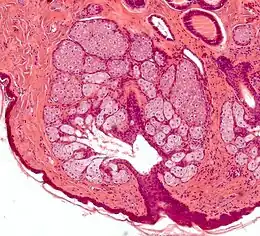

Les glandes sébacées ont une architecture acinaire (en forme de grappe de raisin) et n'ont pas de lumière propre. Elles sont composées de sébocytes matures, dont la sécrétion est le résultat de leur mort par apoptose[pas clair], ce qui revient à une sécrétion holocrine. Le remplacement des cellules est assuré par les cellules de la matrice reposant sur la membrane basale[5].L'annexe pilo-sébacée constituée du follicule pileux, des glandes sébacées et des muscles arrecteurs du poil résulte d'une invagination épithéliale[4].

Annexe pilosébacée avec glandes sébacées s'abouchant à un follicule pileux.

Annexe pilosébacée avec glandes sébacées s'abouchant à un follicule pileux. Multiples glandes sébacées volumineuses réalisant une hyperplasie sébacée.

Multiples glandes sébacées volumineuses réalisant une hyperplasie sébacée. Multiples glandes sébacées s'abouchant à un follicule pileux.

Multiples glandes sébacées s'abouchant à un follicule pileux.